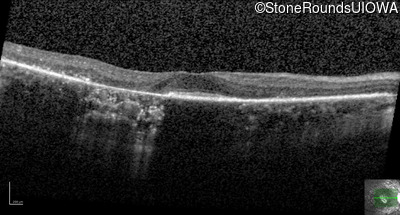

Age at visit: 63 years

This 63 year old woman has had normal vision for most of her life, but recently developed difficulty seeing in dim light.

Diagnosis & molecular findings

AD Retinitis Pigmentosa SAG Cys147Phe TGT>TTT   AD